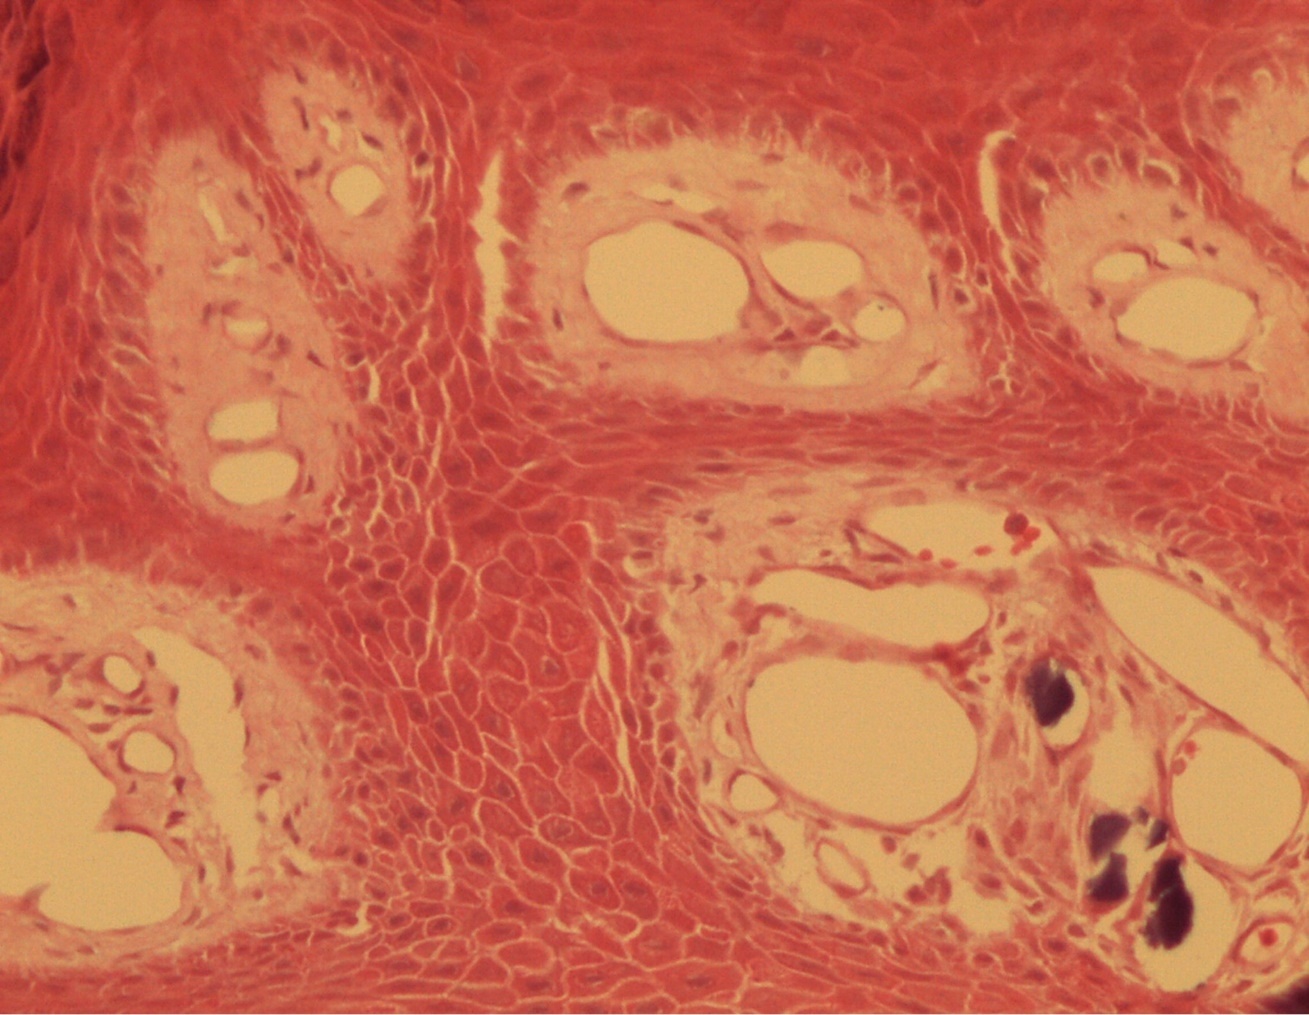

Figure 2.Common wart with calcium foci at the level of the dermal vessels grouped in lobules. HE. 200x.

Common wart with calcium foci at the level of the dermal vessels grouped in lobules. HE. 200x.